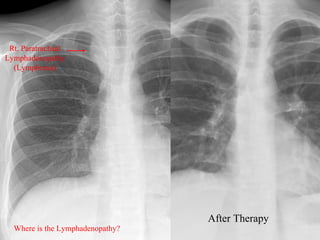

Rt. Paratracheal

Lymphadenopathy

(Lymphoma)

After Therapy

Where is the Lymphadenopathy?

Rt. Paratracheal Lymphadenopathy (Lymphoma) After Therapy Where is the Lymphadenopathy?